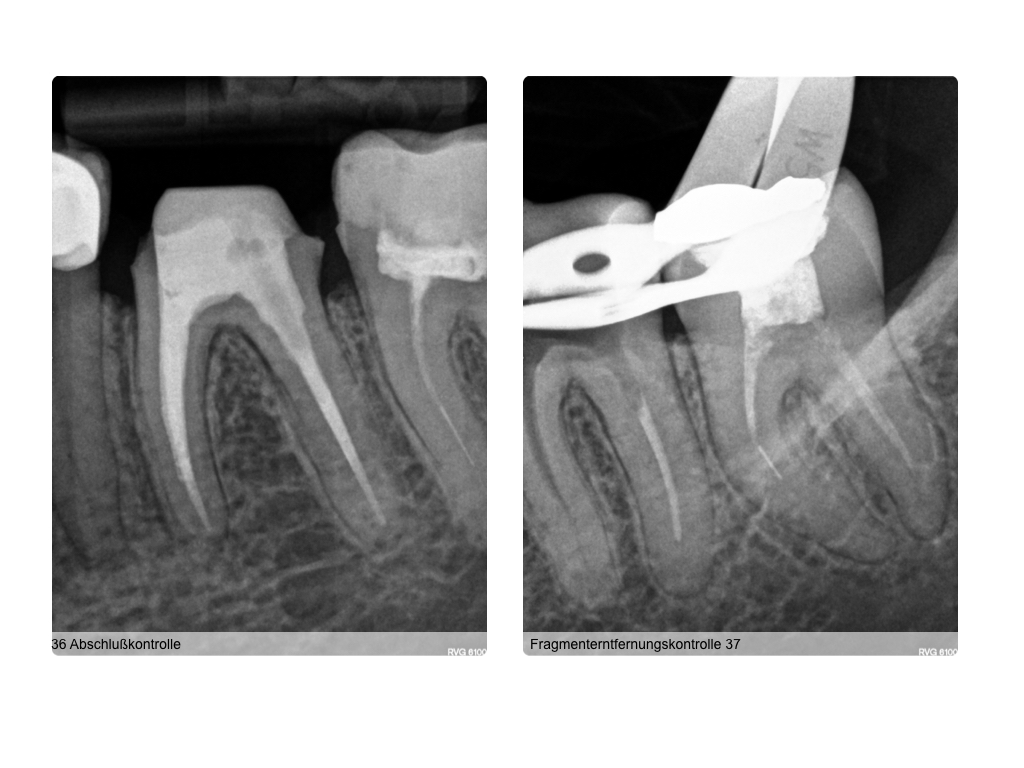

4 auf einen Streich (2)